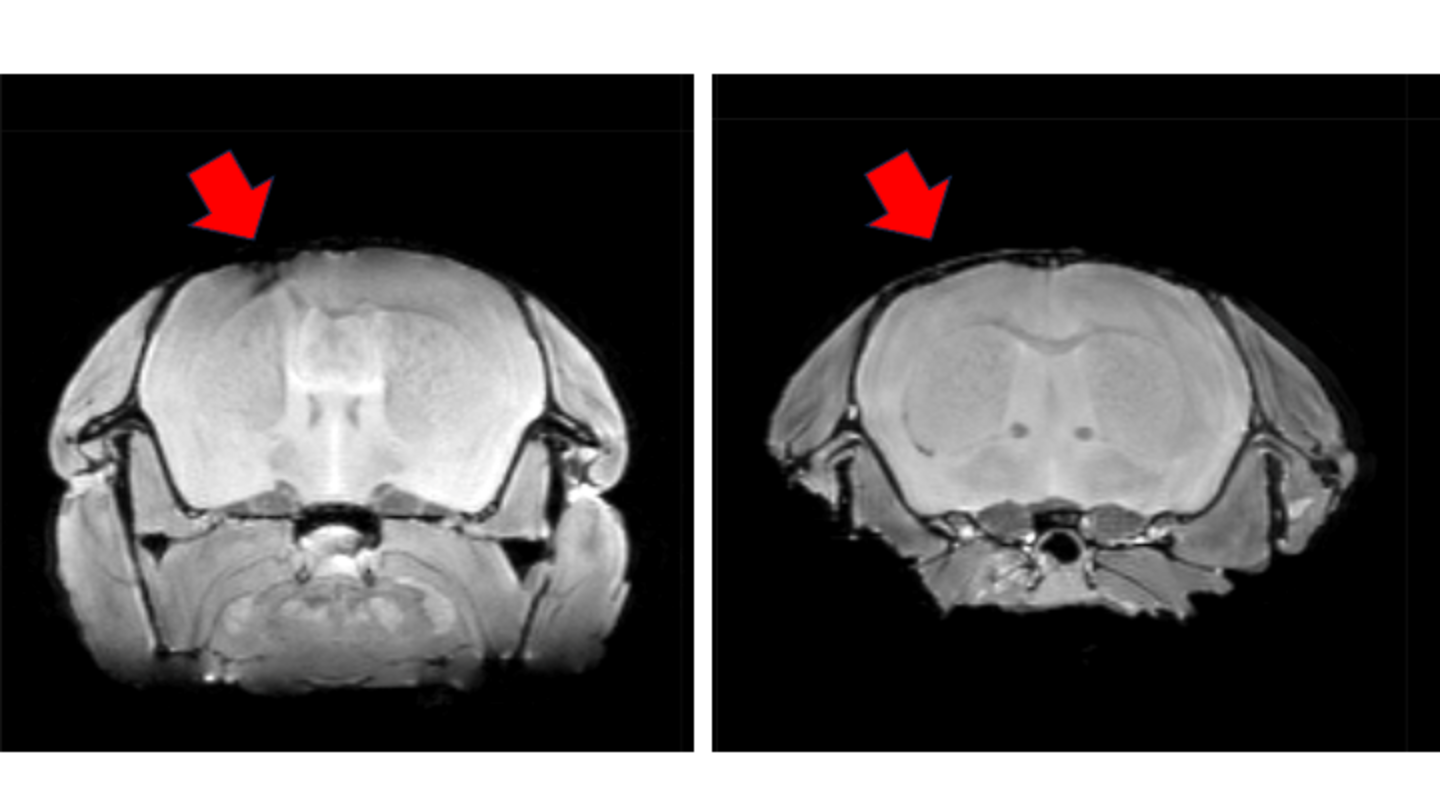

外傷性脳損傷や脊髄損傷により欠損した中枢神経の組織は完全に自然回復することはなく、麻痺や高次脳機能障害などが残存してしまいます。脊髄損傷のiPS細胞を用いた再生治療については慶應義塾大学で臨床治験が始まった一方で、外傷性脳損傷などにおいて失った脳機能を回復させるための再生医療はまだ道半ばであります。私は脊髄損傷の再生治療においては、2つの特許申請を含む実績を積み重ね、それを元に外傷性脳損傷の再生治療に向けた研究を進めています。

特にiPS細胞由来の神経幹細胞・前駆細胞を移植したのちに分化したニューロンの軸索を如何に伸長させるか、また移植されたホスト側の残存組織を如何に活性させるかに着目して研究を進めています。

再生したマウスの脳MRI画像